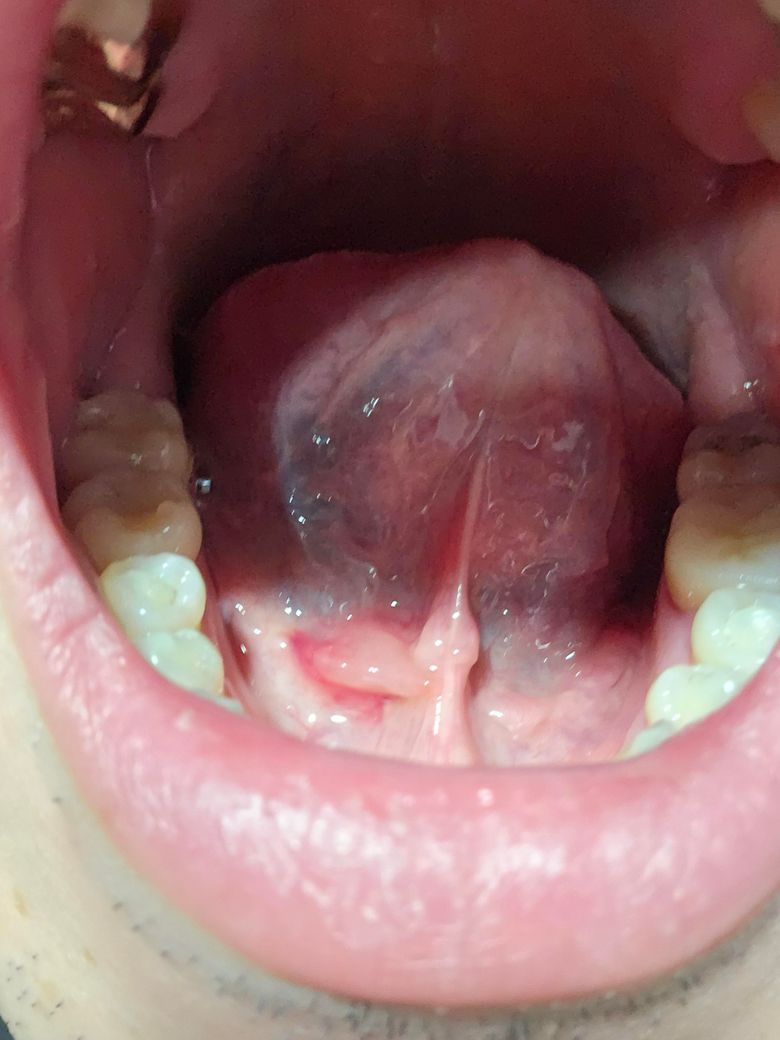

혀 아래 돌기부분이 부었는데 괜찮은가요?

오늘 갑자기 혀아래 돌기부분?오른쪽은 괜찮은데 왼쪽만 이질감이 생기더니 저렇게 부었어요!누르면 통증은 있는데 막 엄청 아푸진않고요.. 알보칠발라야되는건지 이게뭔지.. 걱정되네요 병원은 어디로 가야되는건지도 모르겠어요!ㅠㅠ

혀 밑에 돌기가 생기는 경우 침샘에 염증이 발생하거나 돌이 생겼을 때 발생하는 경우가 있으나 그런 경우에 통증이 동반되는 경우가 많은 편입니다. 따라서 염증성 질환이 아니라면 침 배출로가 폐쇄되면서 부어오르는 하마종과 같은 증상일 가능성이 있기 때문에 이런 경우 치과 등에 방문하셔서 의사의 진찰을 받아보시는 것이 좋겠습니다.

보통 혀 밑에 위치한 침샘에 염증이 생겼을 가능성이 있습니다. 이런 증상은 침샘염이나 침샘에 생긴 결석(침이 잘 배출되지 않아서 염증이 생길 수 있음)일 수 있습니다. 알보칠 같은 구강 세정제는 염증을 완화시킬 수 있지만, 정확한 원인을 알기 위해서는 반드시 이비인후과에서 진료를 받는 것이 좋습니다.